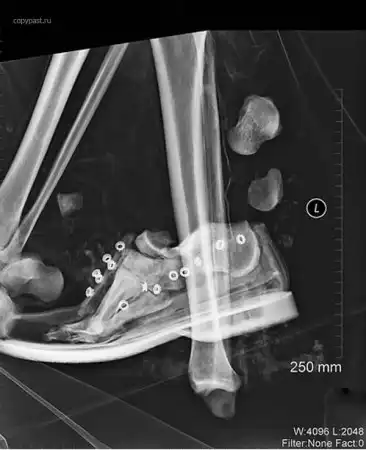

Человек сидел на переднем пассажирском сиденье в автомобиле, закинув ноги на торпеду,

в том месте, где находится подушка безопасности.

Произошла авария на скорости 40 км/ч, сработали подушки.... Вот так была сломана

ступня. Водитель не пострадал.

Я больше никогда туда не положу ноги